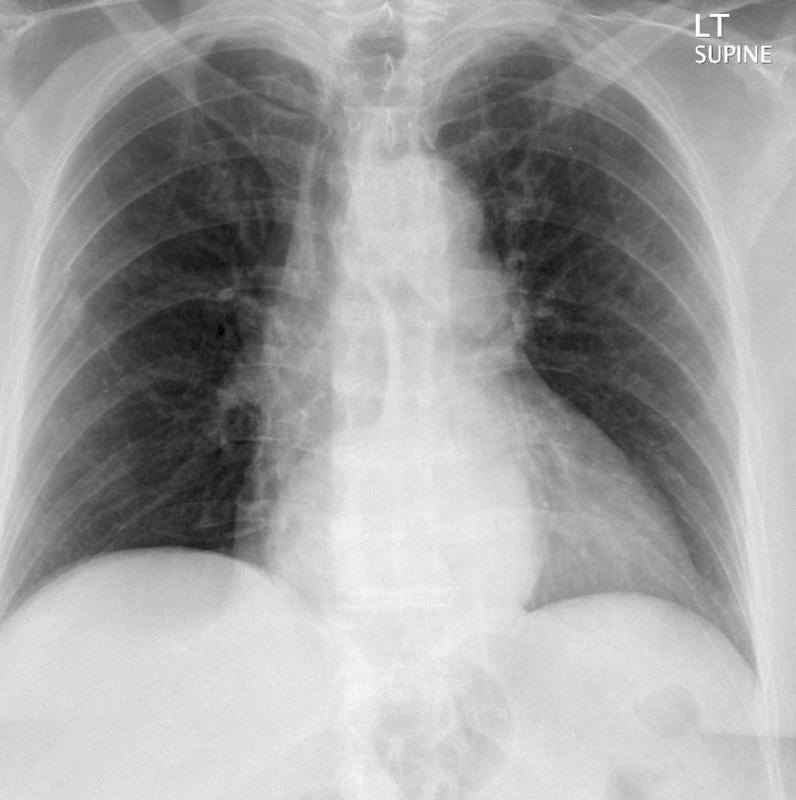

Hiatus Hernia Case 1 PA only

Hiatus Hernia

Case 1 PA only